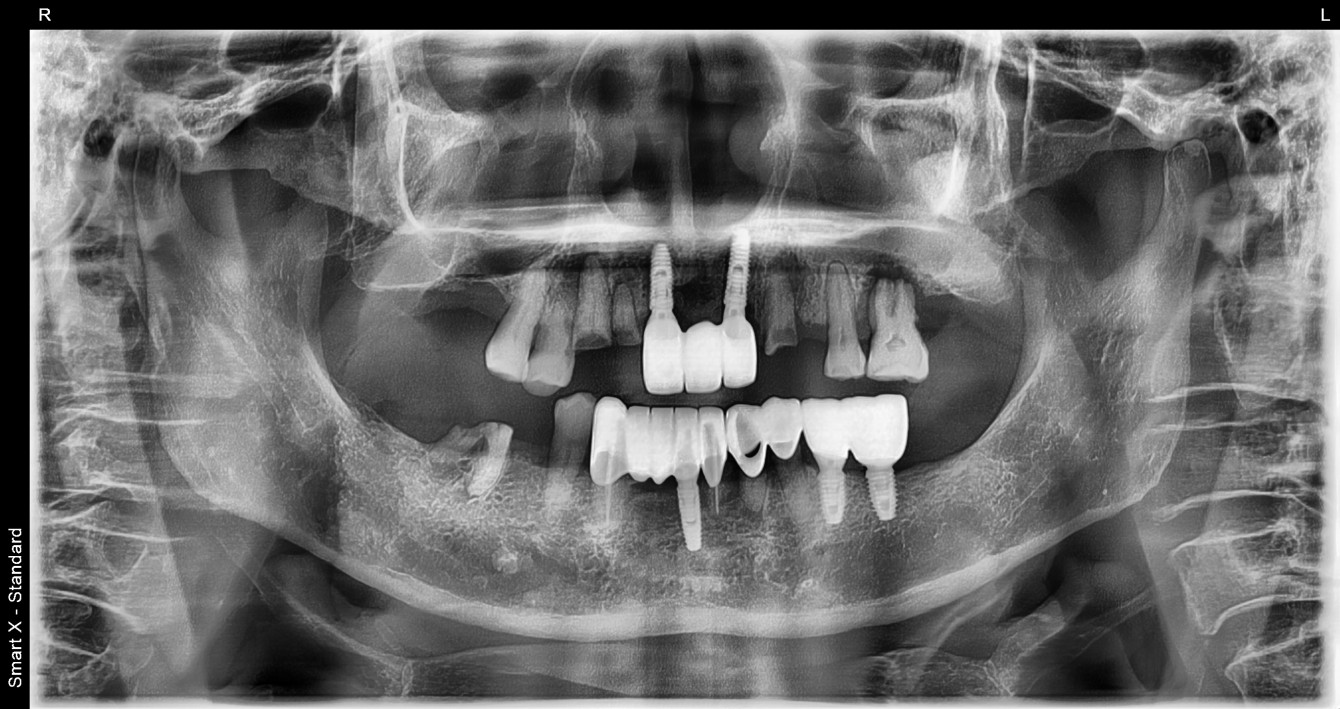

임플란트 | 전악재건 임플란트 케이스 입니다

환자명 이** 치료기간 5개월 한줄 설명 상하악 구치부 전치부를 포함한 전악 재건 임플란트케이스 입니다.